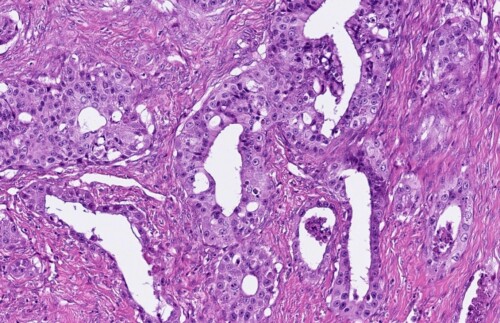

L’examen histopathologique sur la pièce d’exérèse conclut à l’envahissement de l’extrémité digitée par un carcinome peu différencié, avec activité mitotique élevée, absence d’emboles visibles et de caractéristiques morphologiques amenant à privilégier une métastase digitée de carcinome bronchique.

Photos 6 à 8 : Examen histopathologique du doigt.

Prolifération tumorale de nature épithéliale, nettement carcinomateuse, peu différenciée. Elle revêt une architecture lobulaire et plus rarement tubuleuse. Elle est associée à un stroma fibroplasique

abondant. Les cellules néoplasiques sont de grande taille, arrondies à polyédriques, à cytoplasme éosinophile étendu. Les noyaux sont arrondis, volumineux, plutôt vésiculeux, fortement mono ou ou plurinucléolés. L’anisocaryose est nette. L’activité mitotique est élevée. Absence d’images nettes d’embolisation vasculaire. La prolifération tumorale infiltre largement les tissu mous le long des phalanges (Photos Antech LAPVSO)